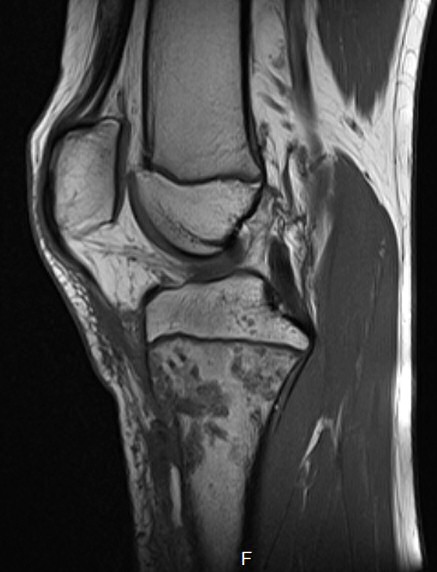

MR-bild av osteomyelit proximala tibia på barn